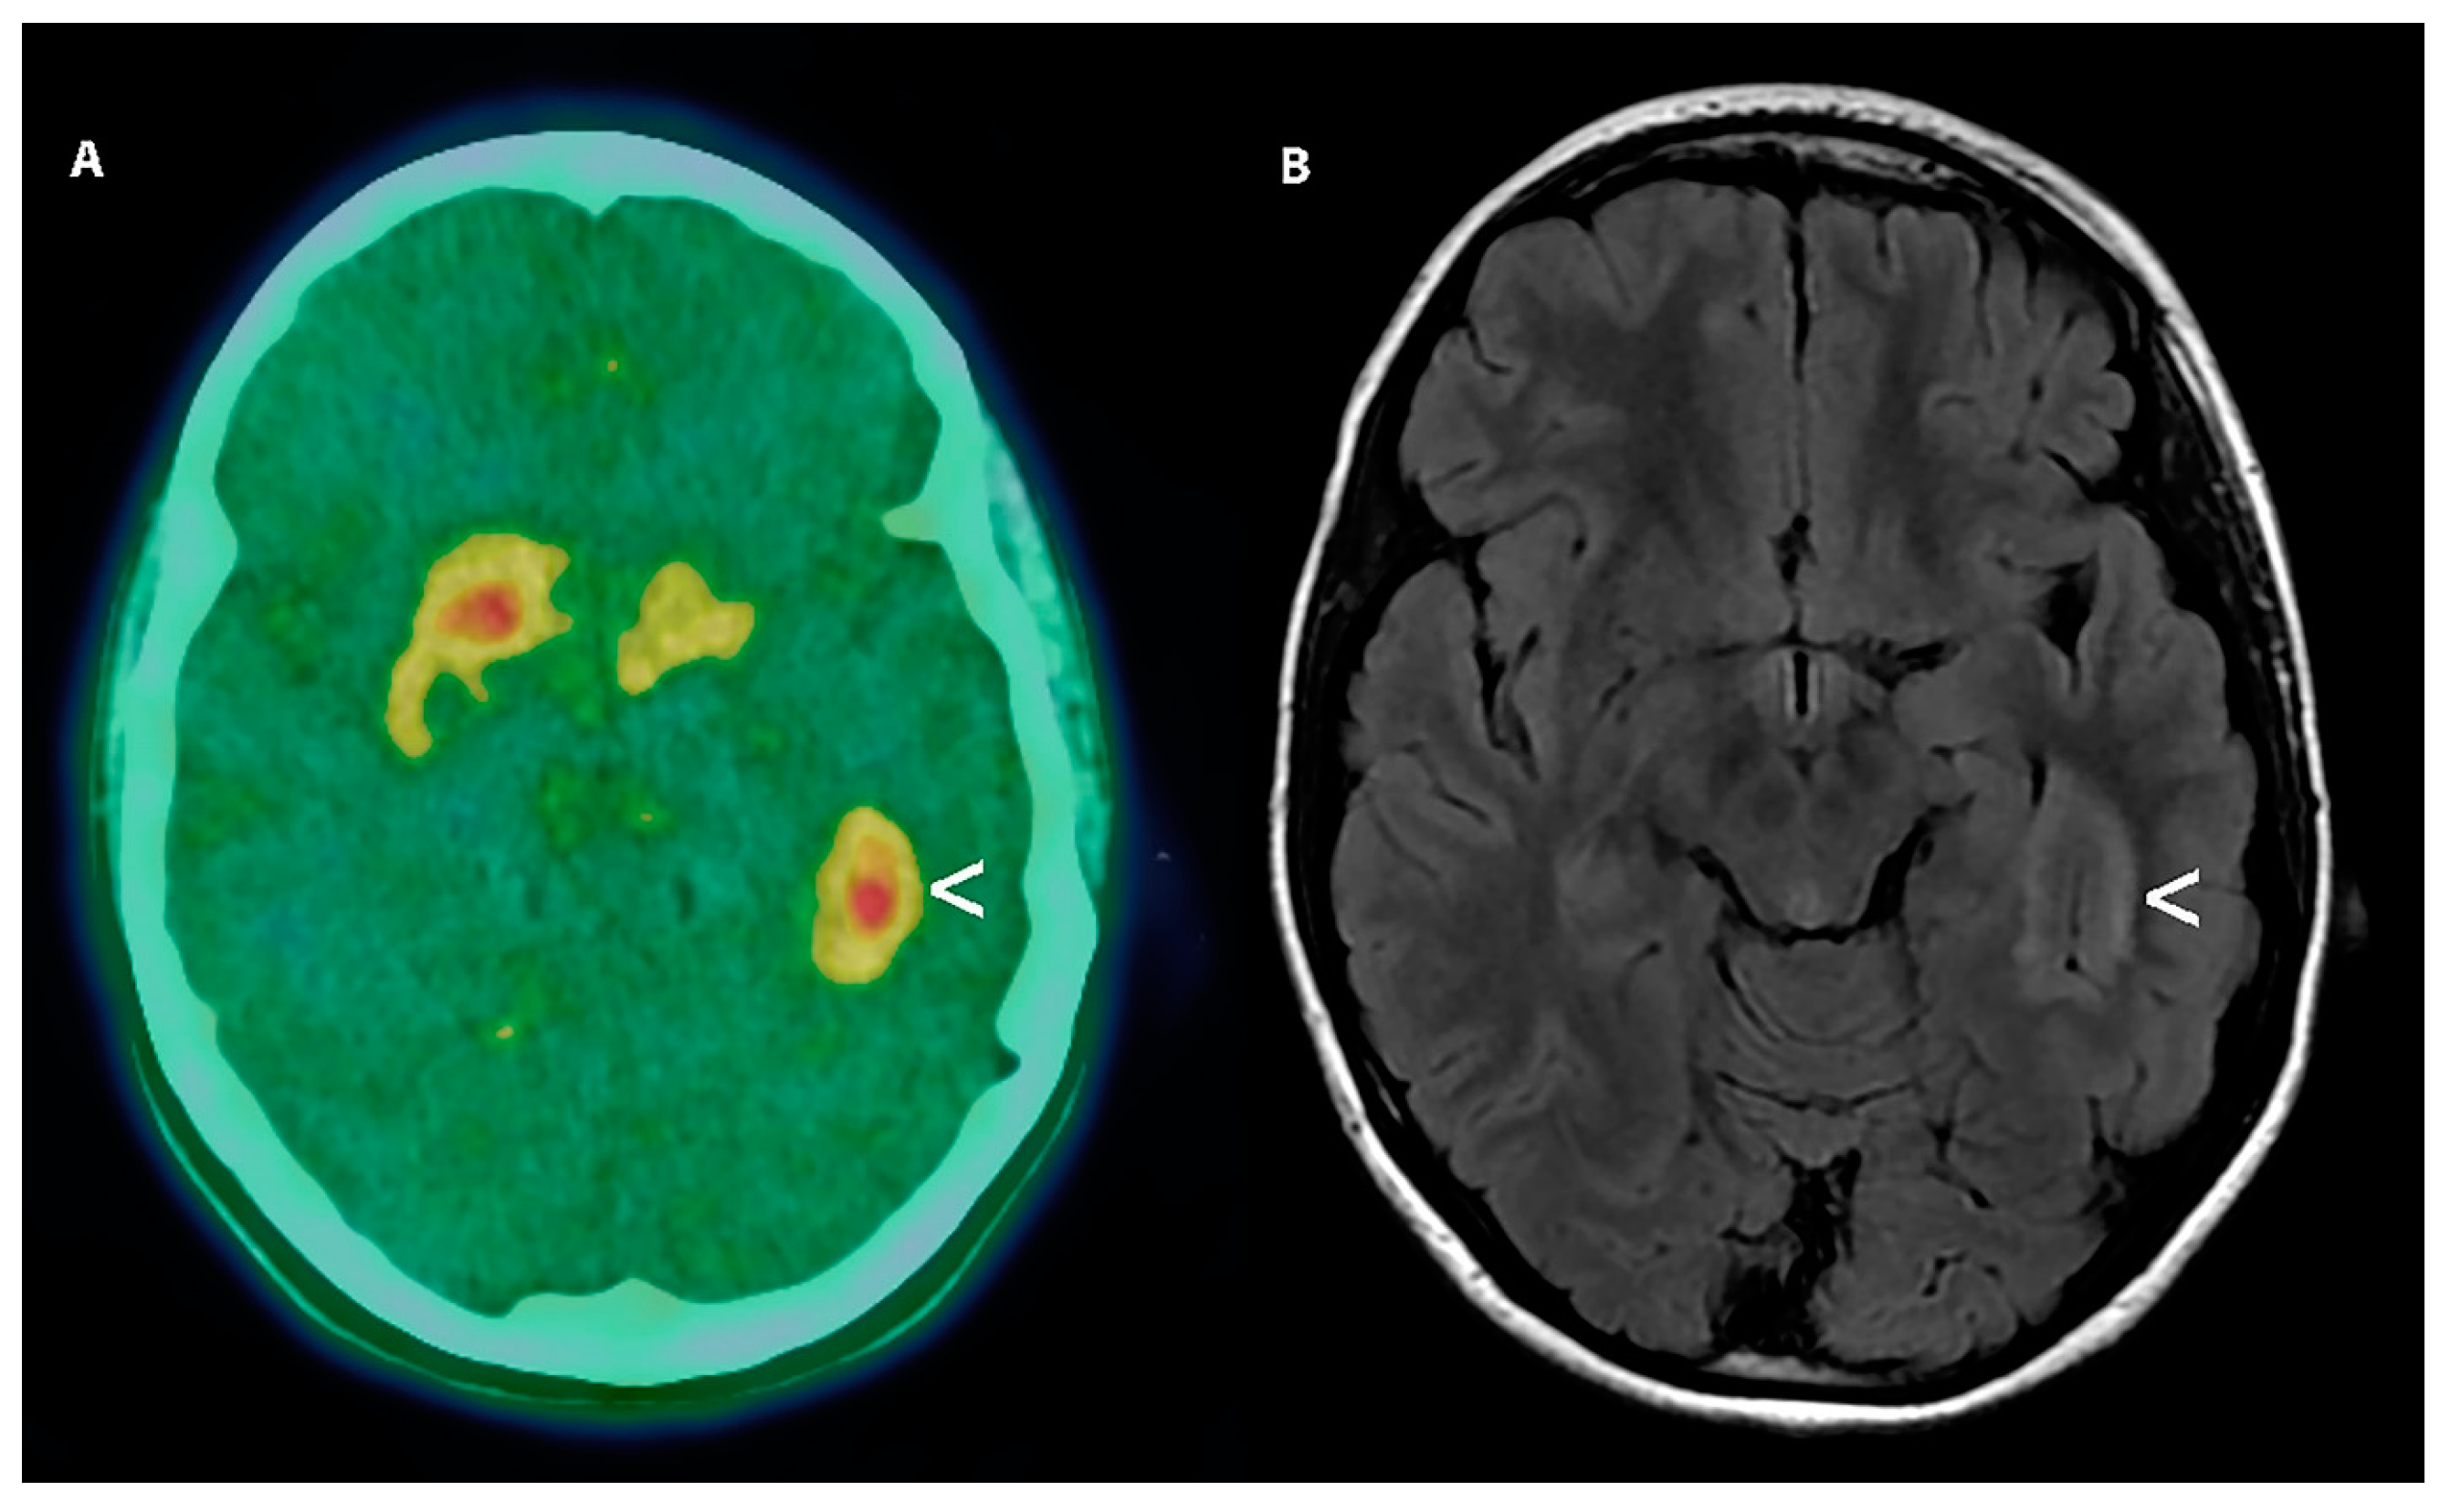

- Morana, G.; Puntoni, M.; Garre, M.L.; Massollo, M.; Lopci, E.; Naseri, M.; Severino, M.; Tortora, D.; Rossi, A.; Piccardo, A. Ability of (18)F-DOPA PET/CT and fused (18)F-DOPA PET/MRI to assess striatal involvement in paediatric glioma. Eur. J. Nucl. Med. Mol. Imaging 2016, 43, 1664–1672. [Google Scholar] [CrossRef]

| Morana et al. [35] | 2016 | [18F] FDOPA | Retrospective study | Pre-operative imaging Monitoring after therapy | N = 28 | The technical paper aimed to investigate the physiological striatal FDOPA uptake in the evaluation of basal ganglia involvement of PBT in PET/TC. | Pediatric |